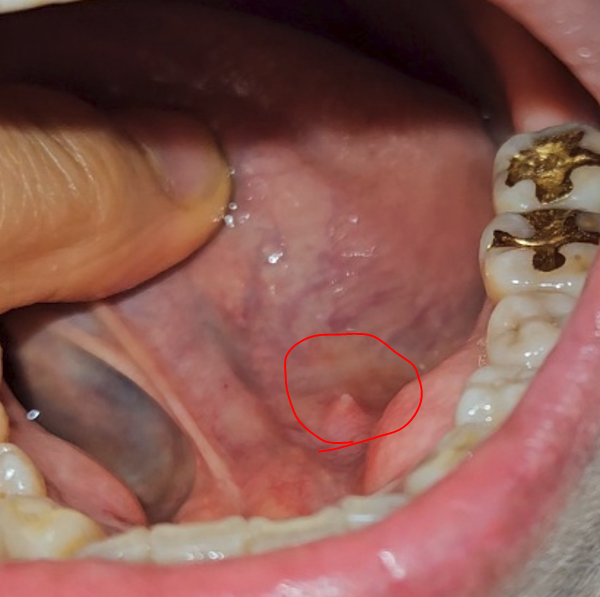

혀뿌리 옆 하얀색 돌기 같은 게 나서 통증이 있어요.

식사하거나 말할 때 통증이 있으시다는데

일종의 혓바늘, 구내염의 한 종류일 것으로 사료됩니다.

혓바늘이 생기면 스치거나 먹을 때 통증을 느낄 수 있으며 말을 하거나 음식을 먹을 때 더 심해질 수 있습니다. 이 증상은 주로 혀 유두에서 나타나 맛을 느끼기 어려울 수 있습니다.